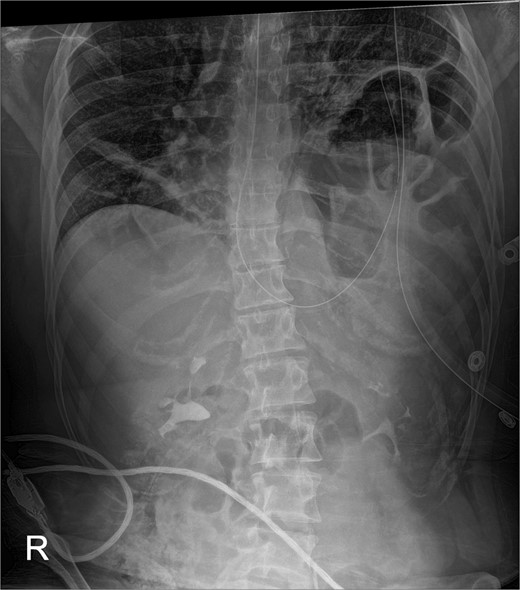

The early postoperative course was unremarkable. The patient reported feeling mild bloating, but was discharged on postoperative Day 1 after removal of a chest tube (Fig. 4). A few hours after discharge from the hospital, he developed dysphagia, progressive abdominal pain, distension, and dyspnea that prompted a return to the hospital. Physical examination revealed tachycardia (132 bpm), mild hypoxia requiring supplemental O2 at 2 L/min via nasal canula, and abdominal distension. Laboratory studies showed WBC of 12 600 cells/μL. A CT scan of the abdomen and pelvis revealed a large, acute organo-axial gastric volvulus without evidence of ischemia, and an intact left hemidiaphragm plication at a similar height to the right hemidiaphragm (Fig. 5). A nasogastric tube was placed with immediate drainage of 1 L of dark bilious fluid with immediate relief of the patient’s symptoms. However, a subsequent film revealed the nasogastric tube projecting toward the upper left chest with presence of colonic haustra (Fig. 6), consistent with acute hemidiaphragm rupture.

Following chest-tube removal, a film was taken, revealing even hemi-diaphragms, which was notably higher than immediate post-operatively, but within normal limits.